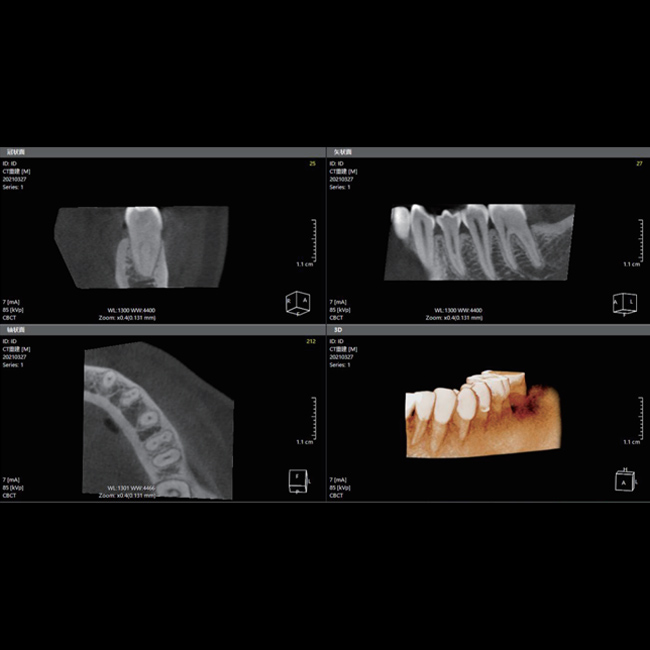

星垂视野 一览无余

采用高性能CMOS探测器,最大FOV可达16x9cm星垂视野并支持无极可调,最小体素0.05mm。头颅采集模式,支持3s超快速扫描,最小像素99um,保证优质影像快速采集。

16x9

最大FOV

0.05mm

最小体素

CMOS

探测器

3s

超快速扫描

支持局部超清三维显示

局部超清显示、 移动视野摄片

真人正侧位投影,实现CT成像区域无极可调

可根据临床需求任意调整成像区域大小实现局部超清三维显示

可根据临床需求任意调整成像区域大小实现局部超清三维显示

临床样片